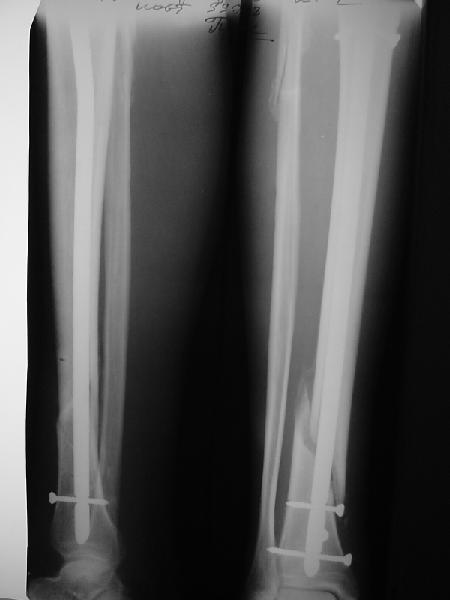

На мой взгляд, на снимках, приведённых Вами - неправильно сростающийся перелом дистальной трети большеберцовой кости, состояние после остеосинтеза интрамедуллярным гвоздём.

Как Вы пишите снимок под номером 1 - менсяц после операции, под номером 2- два месяца после операции.

I think that the X-Rays show S/P IMN of Spiral # of the Distal Tibia consoles in misalignment.

You wrote that a picture number 1 - f month after the surgery, and number 2-two months after the surgery.

Ok. А также и следующий, в 3 месяца.